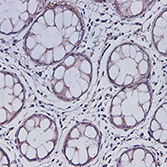

IHC;IF

WB;IHC

WB;IHC

WB;IHC;IF

IHC